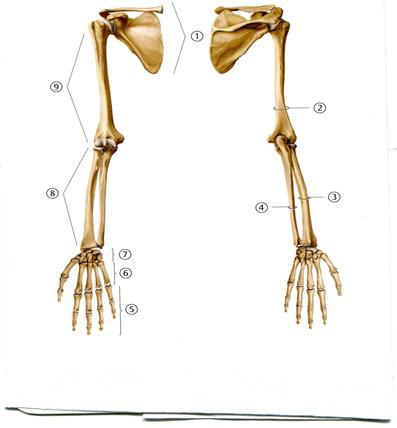

48. Төменде көрсетілген суреттегі белгіленген № 4 анатомиялық құрылымды атаңыз.

А. Акромиальді өсінді

+В. Кіші төмпешік

С. Құстұмсық тәрізді өсінді

D. Төмпешікаралық жүлге

Е. Үлкен төмпешік

51. Төменде көрсетілген суреттегі белгіленген № 4 анатомиялық құрылымды атаңыз.

А. Алақан сүйектері

В. Білезік сүйектері

С. Жауырын

D. Кәрі жілік

+Е. Шынтақ сүйек